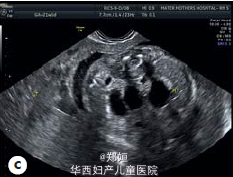

22岁初产妇,孕21周,因胎儿膀胱未见、羊水过少、胎儿腹部囊性结构就诊

B超提示羊水过少和未见胎儿膀胱,肾窝内未见肾脏,但是在腹腔和盆腔可见三个囊性结构,外生殖器性别不明 胎儿MRI提示有泌尿生殖器畸形

临床诊断为胎儿泌尿生殖器畸形 患者要求生产,在孕35周,顺产生下一3140g男婴